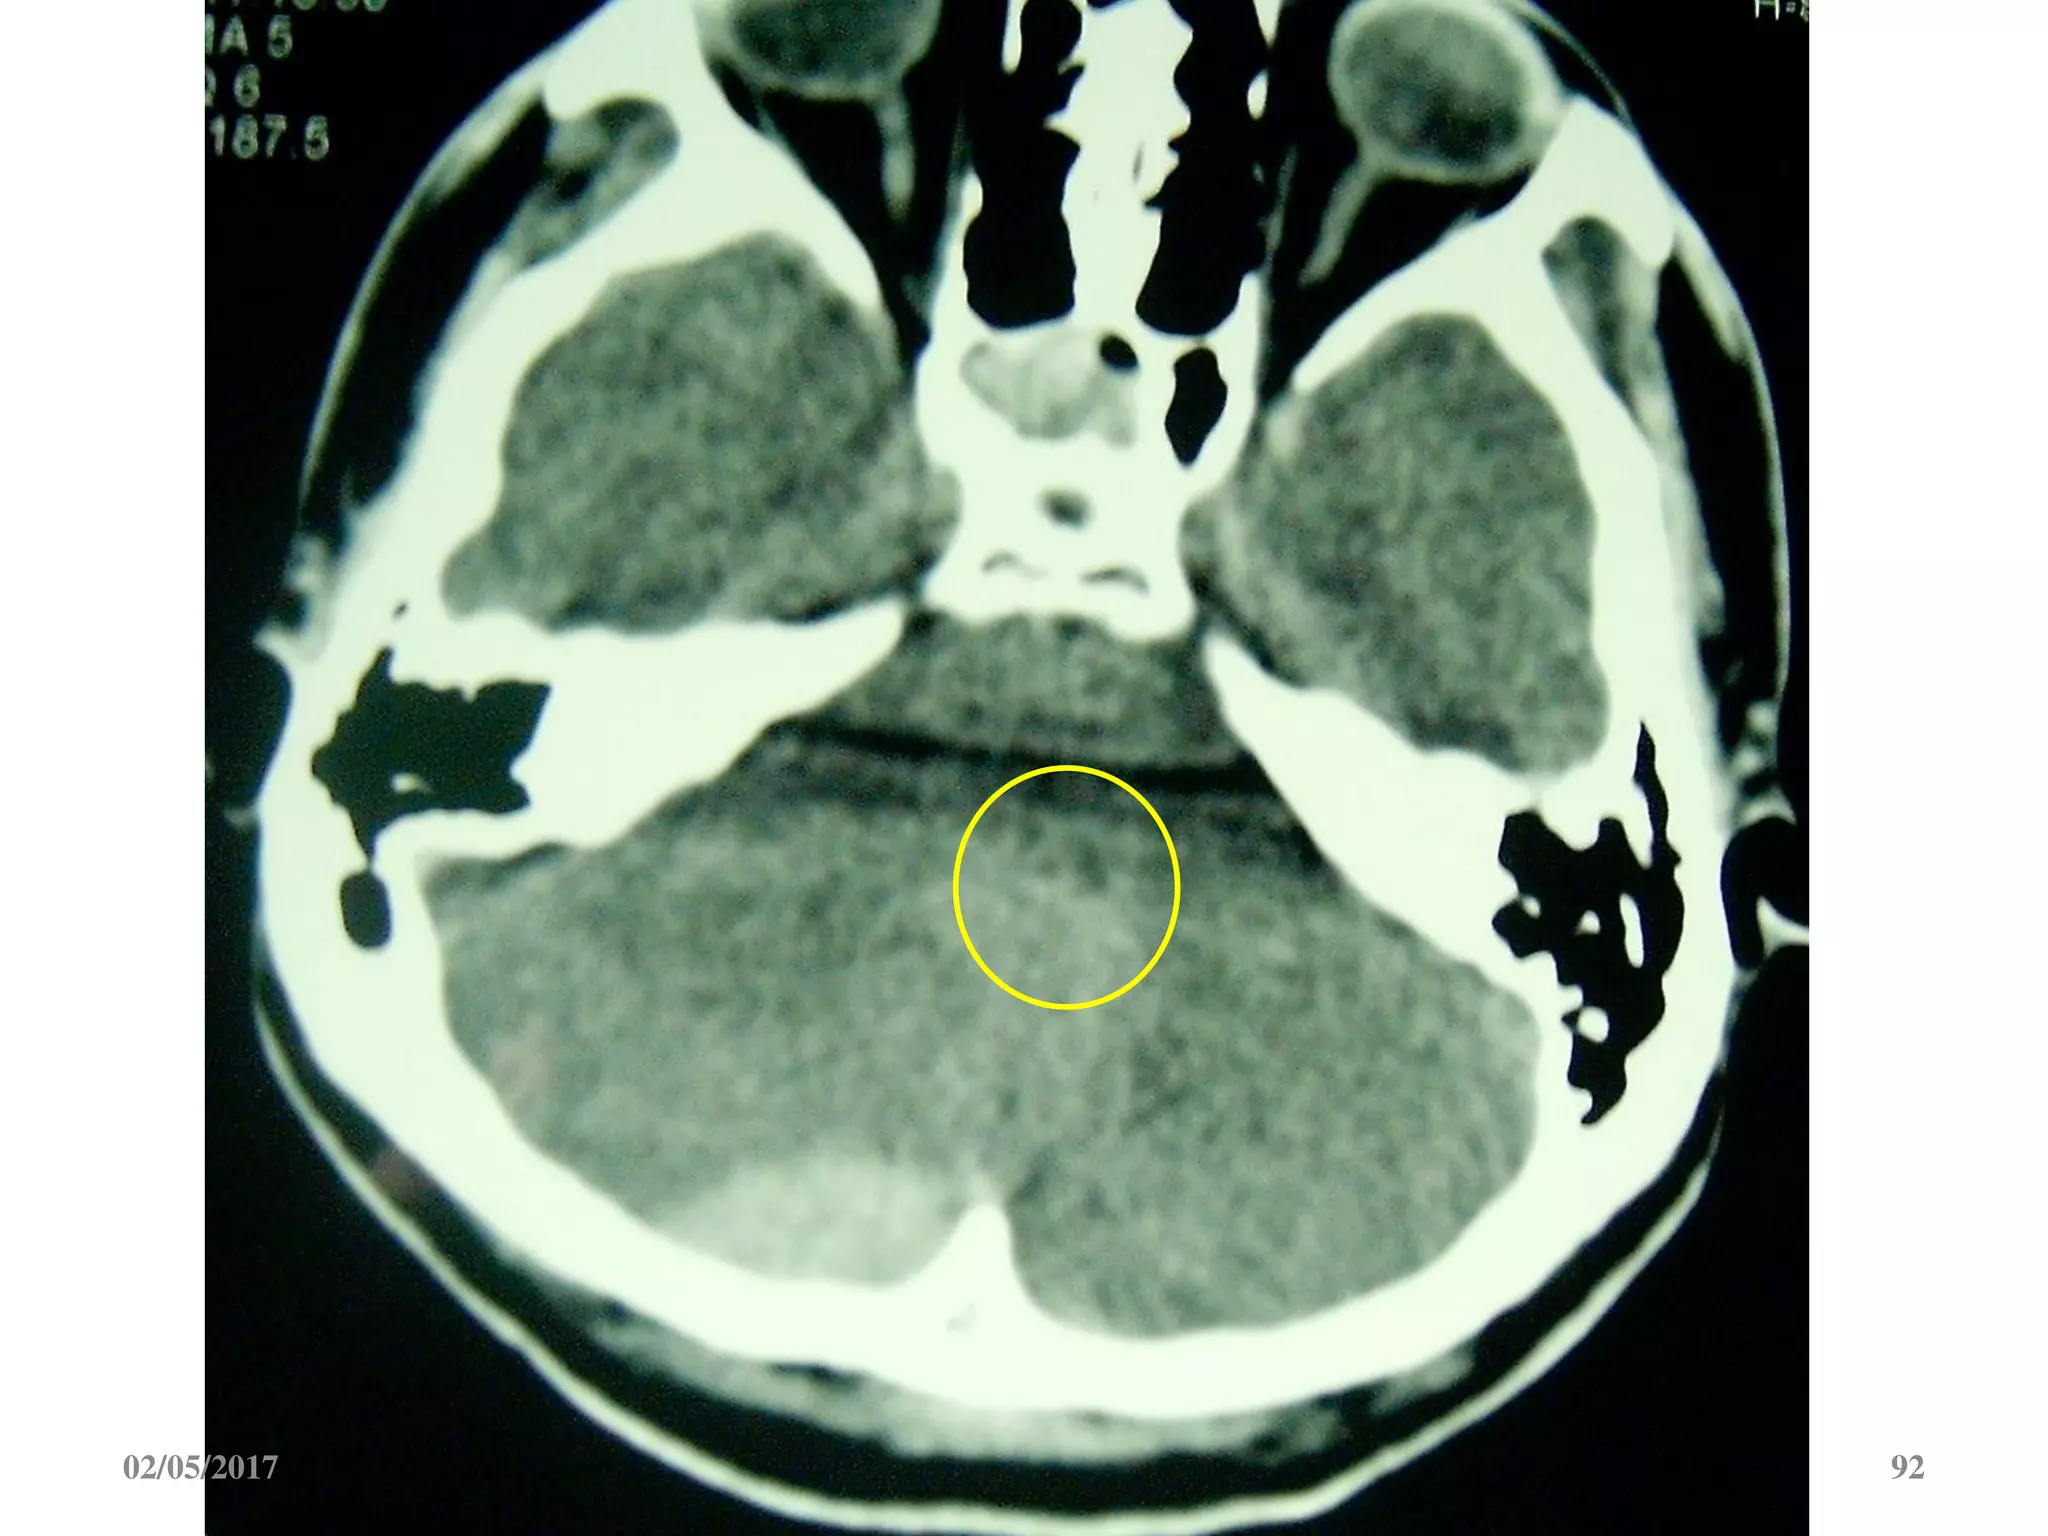

 Máu tụ hố sau gây chèn ép não thất 4.

3. Máu tụ hố sau: xóa mất, đẩy lệch não thất 4